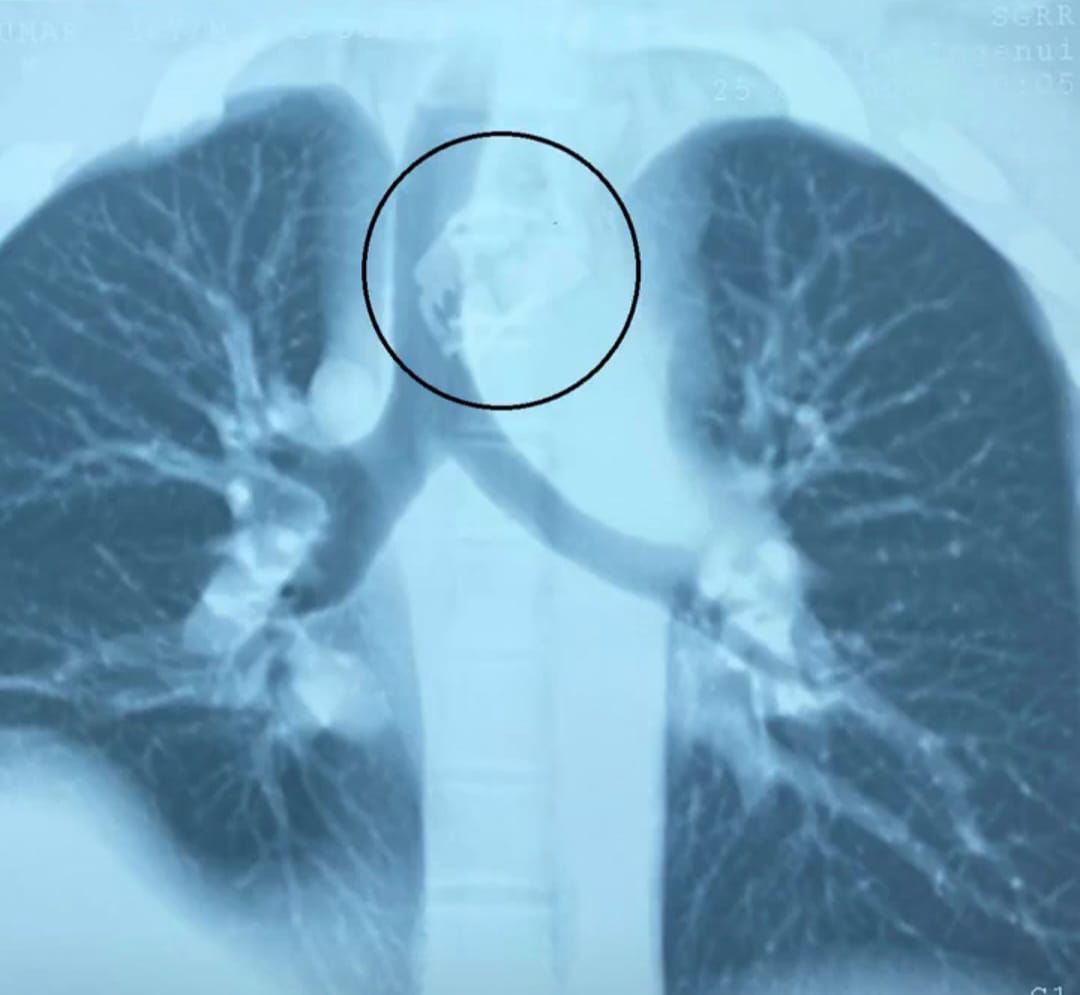

डाक्टरों ने मरीज का ऑपरेशन कर ब्लेड को आहार नाल यानी (खाने की नाला) से सफलतापूर्वक बाहर निकाला।ऑपरेशन के बाद मरीज बिल्कुल ठीक है। यह जानकारी इंद्रेश अस्पताल के नाक कान गला रोग विभाग के डाॅ शरद हरनोट ने दी। 26 वर्षीय पुरुष भूलवश खाने के साथ रेज़र ब्लेड निगल गए। खाने की नली में फंसे धारदार ब्लेड की वजह से मरीज के जीवन पर बन आई थी।

इंद्रेश अस्पताल के नाक कान गला रोग विभाग के डाक्टरों ने प्रारम्भिक जांच में पाया कि ब्लेड सांस की नली के पास महत्वपूर्ण खून की सबसे बड़ी नस के काफी पास अटकी हुई है। इंद्रेश अस्पताल के नाक कान गला रोग विभाग के डॉक्टरों ने 26 वर्षीय पुरुष की खाना खाने की नली में फसे रेजर ब्लेड को निकालकर मरीज को नया जीवन दिया है ।

श्री महंत इंद्रेश अस्पताल के असिस्टेंट प्रोफेसर व ईएनटी सर्जन डॉक्टर शरद हरनोट ने सीनियर रेजिडेंट डॉ. फातमा अंजुम के साथ मरीज की सफल सर्जरी की और एंडोस्कोपी द्वारा पूर्ण रेजर ब्लेड को खाने की नली से बाहर निकाला। मरीज के माता पिता ने डॉक्टरों व श्री महंत इंद्रेश अस्पताल का आभार जताया।

ऑपरेशन अत्यधिक जटिल था। ऑपरेशन के बाद मरीज को नाक की नलकी द्वारा उपचार एवम खाना शुरू किया गया। ऑपरेशन के बाद मरीज बिल्कुल ठीक है।